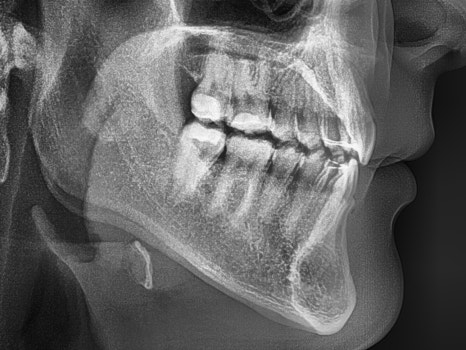

1. 초진

앞에서 봤을 때

하악 전치부들이 상악 전치부에

많이 가려져 있는 것을 볼 수 있습니다.

이런 딥바이트는 그대로 두면,

여러 부작용이 나타나게 됩니다.

치아들의 교합면이 빨리 마모가 되면서,

시끈거리거나 지끈거리는 느낌을 받을 수 있고

턱 관절 디스크가 터지거나 욱신거림 등의

증세가 나타날 수 있습니다.

실제로 저희 인비절라인 후기 치과에 오셨던

이 환자께서도 구강 내에

여러 문제들을 갖고 계셨었습니다.

앞니는 양 옆으로 벌어진 형태였으며

양쪽 절단연이 비대칭적인

모습을 갖고 있네요.

어금니 뒤쪽은 배열에서 벗어나

삐뚤어져 있는 총생을 갖고 있었습니다.

이를 크라우딩(crowding)이라 부릅니다.

맨 뒤에있는 어금니가 올바른 맞물림이 아니라

바깥 쪽으로 뻐드러져 교합이 되지 않고 있었는데요.

다행히 골격적인 문제는 없었으나

심한 딥바이트로 인해 저작이나 절단 등

치아 기능이 제대로 되지 않고 있었습니다.